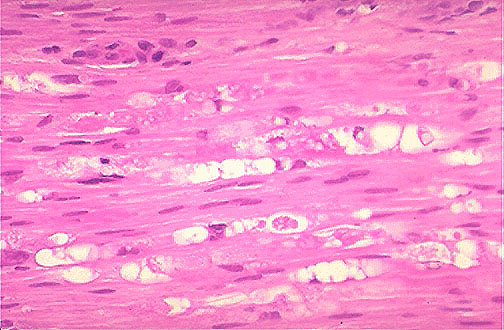

| This is Wallerian degeneration seen distal to the site of a traumatic transection in a peripheral nerve. Regeneration is possible as the proximal nerve stump undergoes axonal sprouting and Schwann cells proliferate to remyelinate the nerve fiber. Regeneration proceeds along the course of the degenerated axon at a rate of about 2 mm per day. |